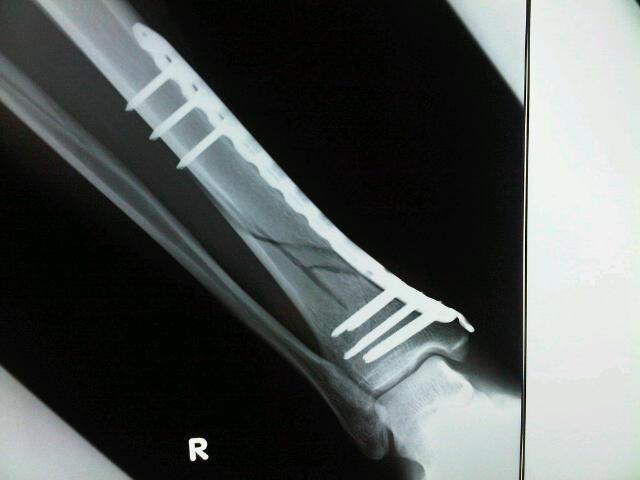

術後3週間の様子です。

明日、ひとまず退院いたします